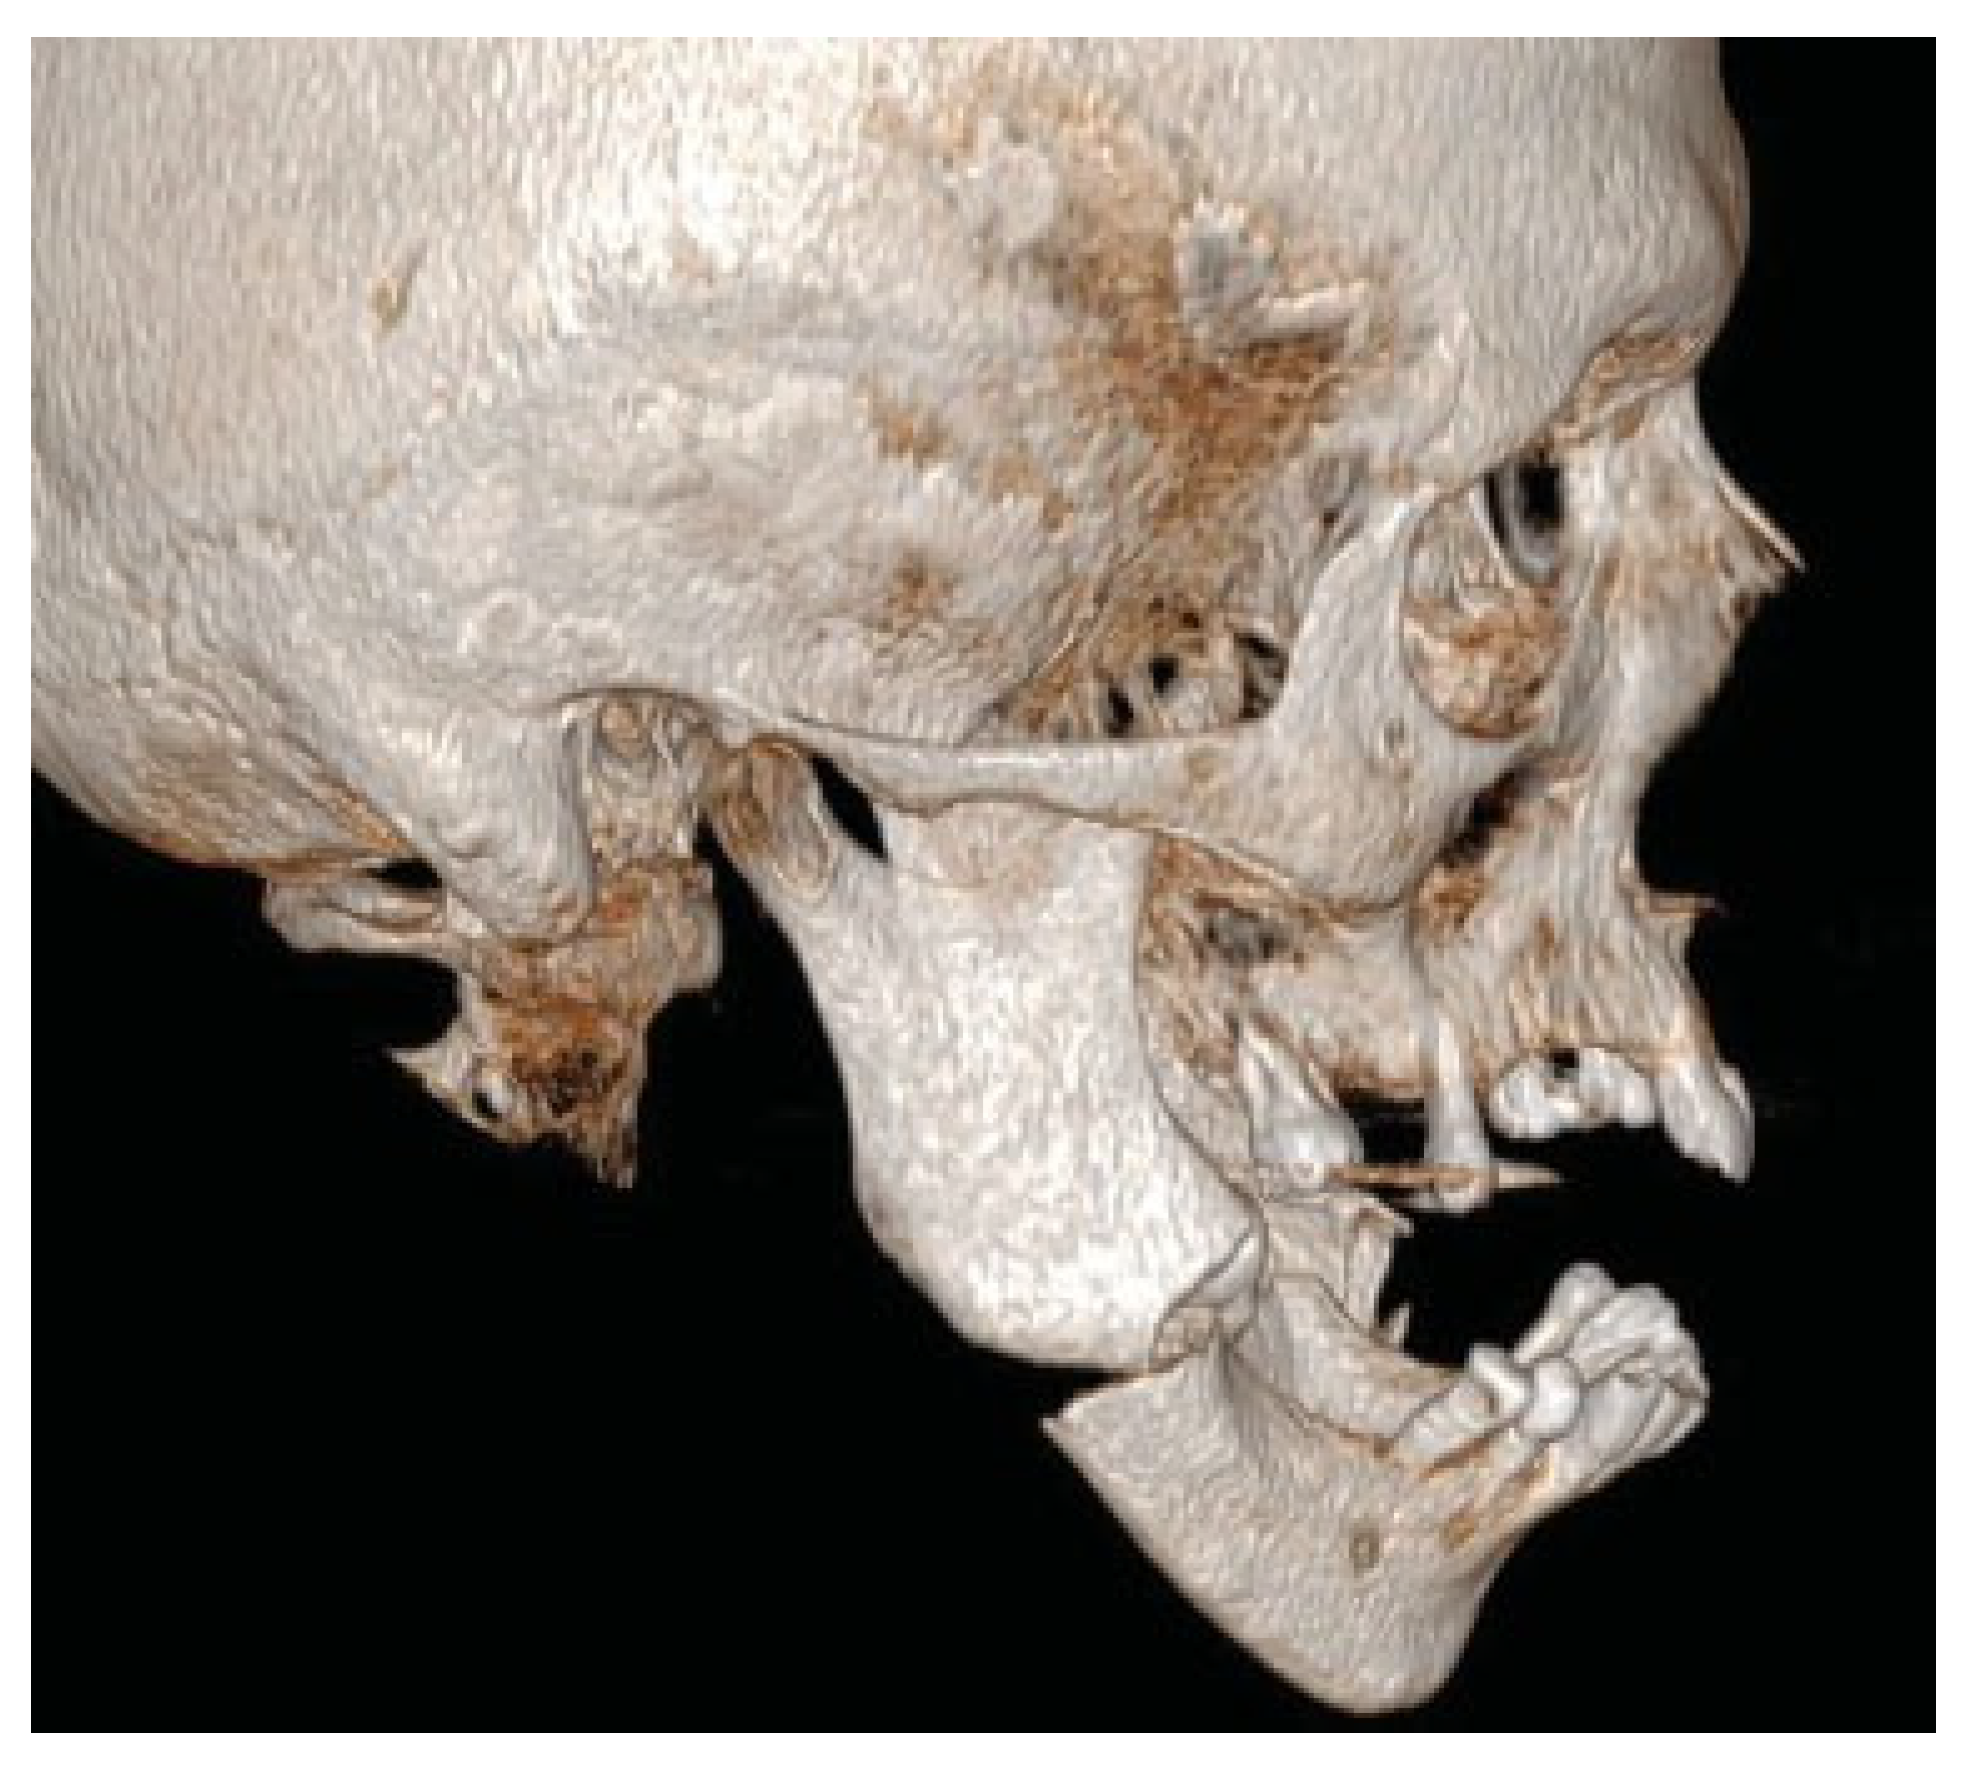

Figure 3.

Patient developed infections with oral mucosal fistulas in the fracture areas and an open bite. CBCT displays obvious anterior rotation of proximal segments and posterior rotation of the dentate part of mandible. Considerable muscle action creates new dislocation and is not counteracted by the inadequate osteosynthesis of the fractures.